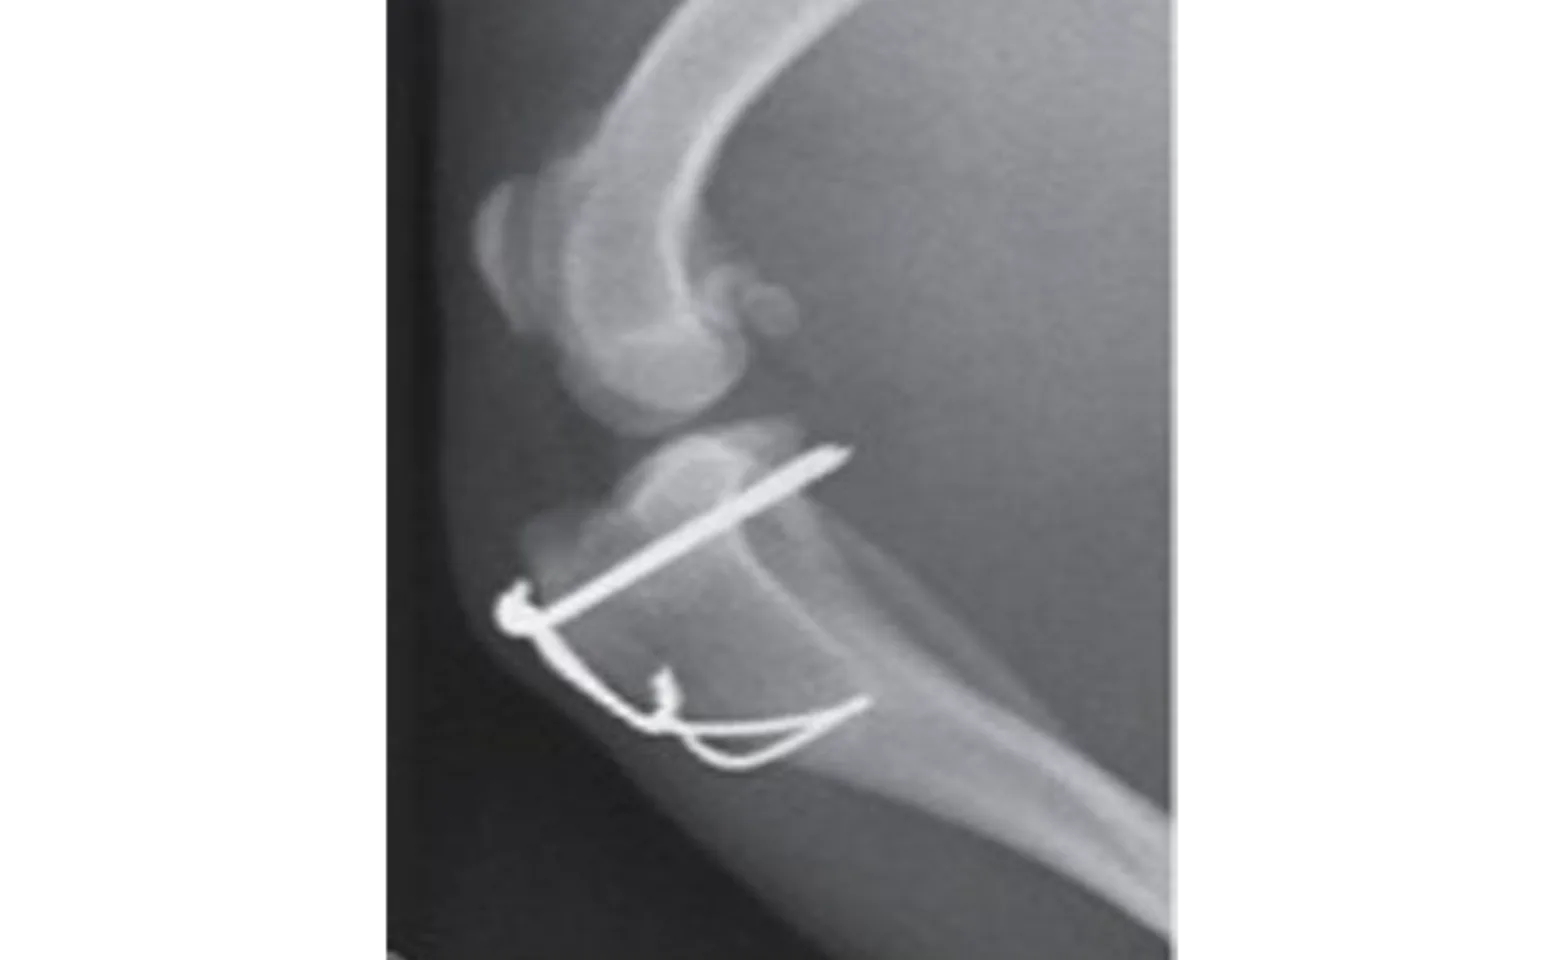

A tibial tuberosity transposition is a procedure in which the insertion of the patellar ligament is moved to assist with re-alignment of the patella. In order to do this a small portion of the bone is cut and moved laterally in direction. For this to heal one or more pins and sometimes wires are required to stabilize the bone fragment.

Image obtained from Tobias and Johnston: Veterinary Surgery Small Animal